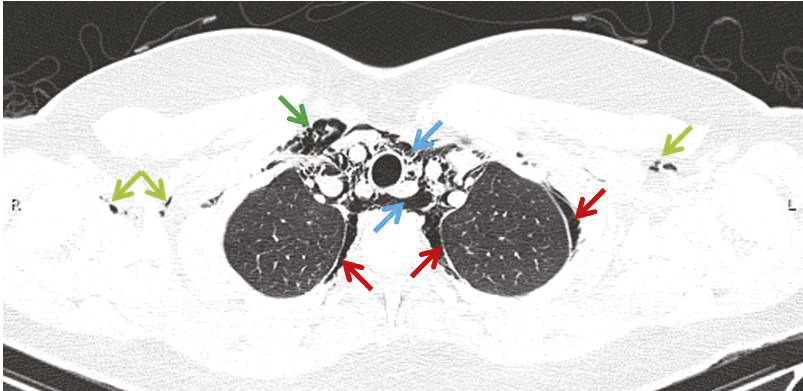

Cette adolescente de 15 ans consultait pour une douleur médiothoracique et cervicale évoluant depuis quelques heures, et une dyspnée sifflante présente depuis 2 jours. Elle avait pour antécédents un eczéma dans la petite enfance et une rhinite allergique. L’examen physique notait des sibilants bilatéraux, une crépitation à la palpation du cou et des creux sus-claviculaires, et une tachycardie régulière avec crépitation rythmée par les bruits du cœur. La saturation en oxygène était à 94 % en air ambiant. La radiographie thoracique (fig. 1) montrait des clartés fines linéaires délimitant le bouton aortique et un emphysème sous-cutané cervico-thoracique, permettant le diagnostic de pneumomédiastin spontané, compliquant une exacerbation d’asthme. Le diagnostic était confirmé par la tomodensi-tométrie(fig. 2). La patiente était surveillée en soins intensifs pendant 72 heures, avec un traitement par corticoïdes systémiques et aérosols de broncho-dilatateurs, puis un traitement de fond par corticostéroïdes inhalés. L’évolution était favorable, avec régression spontanée du pneumomédiastin.

L’exacerbation d’un asthme est la cause la plus fréquente de pneumomédiastin spontané chez l’adolescent,1 par rupture des alvéoles en périphérie des lobules du fait de l’hyperpression intrathoracique. Une douleur brutale, latérothoracique puis médiane, irradiant vers le cou est très évocatrice. L’examen physique montre un emphysème sous-cutané cervical et sus-claviculaire et une crépitation synchrone des bruits du cœur. La radiographie et la tomodensitométrie thoraciques permettent le diagnostic. L’évolution du pneumomédiastin est, en règle générale, spontanément favorable en 72 heures.2